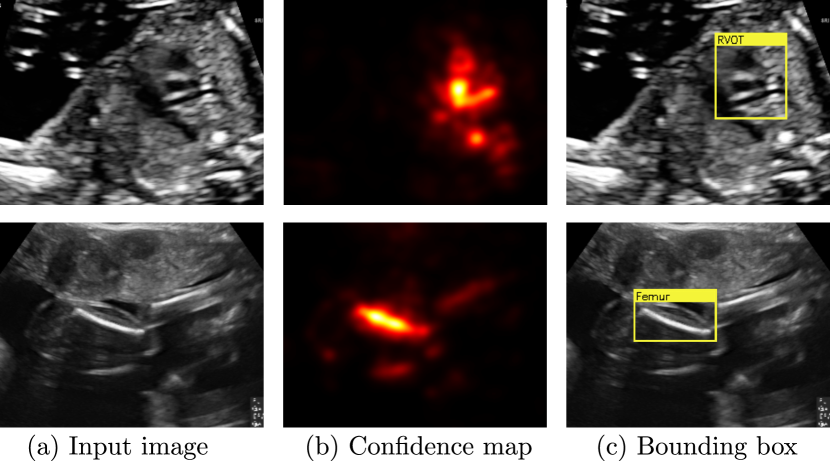

Figure 4: Examples of saliency map post-processing for two challenging views: (a) shows two input images, (b) shows the resulting confidence maps for those images, and (c) shows the resulting bounding boxes.

Next, we post-process saliency maps obtained using Eq. 4 to obtain confidence maps from which we then calculate bounding boxes. In a first step, we take the absolute value of the saliency map S𝑆S and blur it using a 5x55𝑥55x5 Gaussian kernel. This produces confidence maps of the location of the structure in the image such as the ones shown in Fig. 4b. Note that even though both structures are challenging to detect on those views, the confidence maps localise them very well, despite artefacts (shadows in row 1) and similar looking structures (arm in row 2).

Due to the way the gradient is calculated structures that appear dark in the images (such as cardiac vessels) will usually have negative saliencies and structures that appear bright (bones) will usually have positive saliencies in Sksubscript𝑆𝑘S_{k}. We exploit this fact to introduce some domain knowledge into the localisation procedure. In particular, we only consider positive saliencies for the femur, spine and lips, and we only consider negative saliencies for all cardiac views. We use both positive and negative for the remainder of the classes.

Next, we threshold the confidence maps using the Isodata thresholding method proposed in [10]. In the last step, we take the largest connected component of the resulting mask and fit the minimum rectangular bounding box around it. Two examples are shown in Fig. 4c.